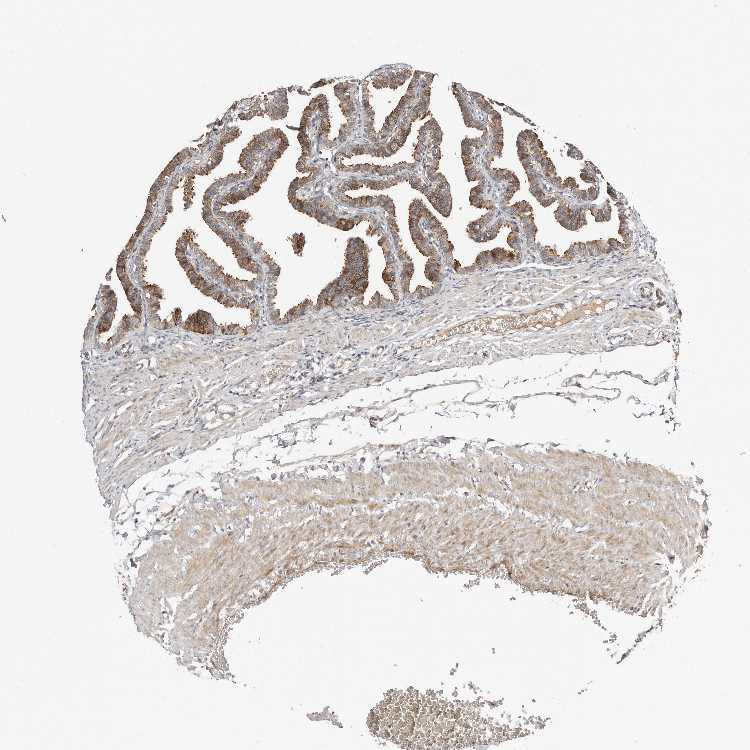

FALLOPIAN TUBE - Antibody stainingi

Antibody staining in the annotated cell types in the current human tissue is reported as not detected, low, medium, or high, based on conventional immunohistochemistry profiling in selected tissues. This score is based on the combination of the staining intensity and fraction of stained cells.

Each image is clickable and will lead to virtual microscopy that enables deeper exploration of all samples and also displays staining intensity scores, fraction scores and subcellular localization as well as patient and tissue information for each sample.

Antibody HPA027863

Glandular cells Medium